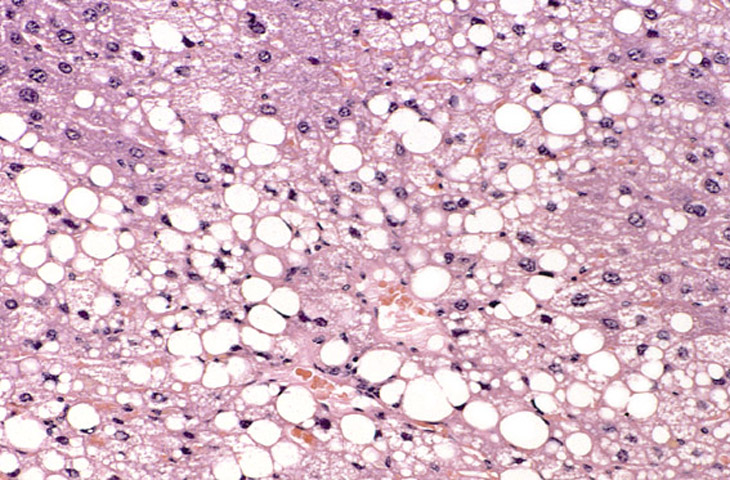

Large areas of fatty change without a distinct lobular pattern are present in this liver. The large, sharply delineated, clear vacuoles represent macrovesicular fat that has been dissolved during tissue processing. Deposition of fat in the hepatocyte cytoplasm often displaces the hepatocyte nucleus to the periphery of the cell.